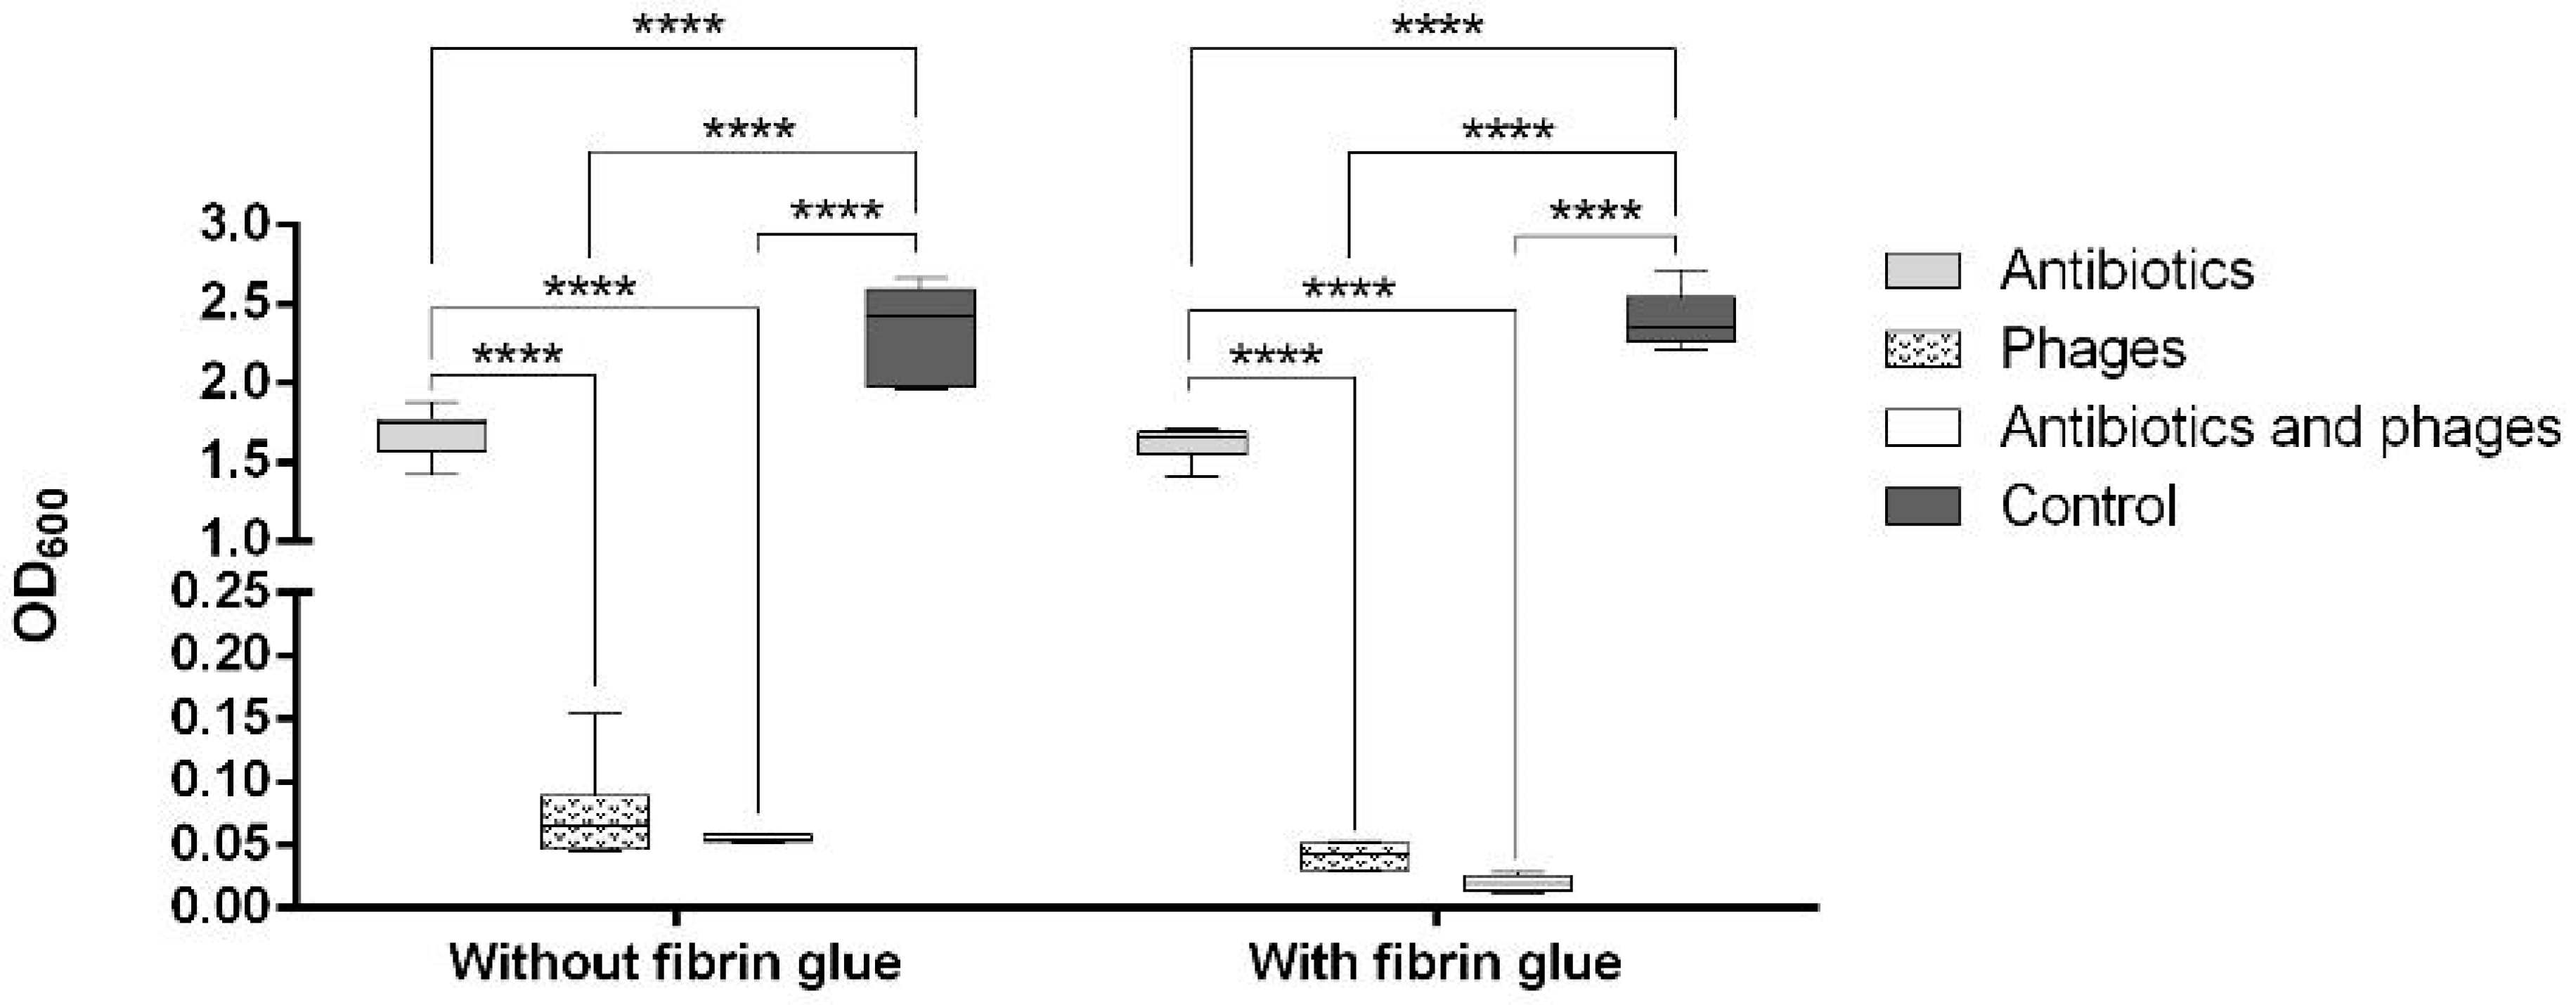

2.2. Antibacterial Loads of Graft Samples

2.2.1. Uncoated Grafts

2.2.2. Coated Grafts

2.3. Antibacterial Activity against Single Contamination

2.3.1. Activity against Staphylococcus aureus

2.3.2. Activity against Escherichia coli